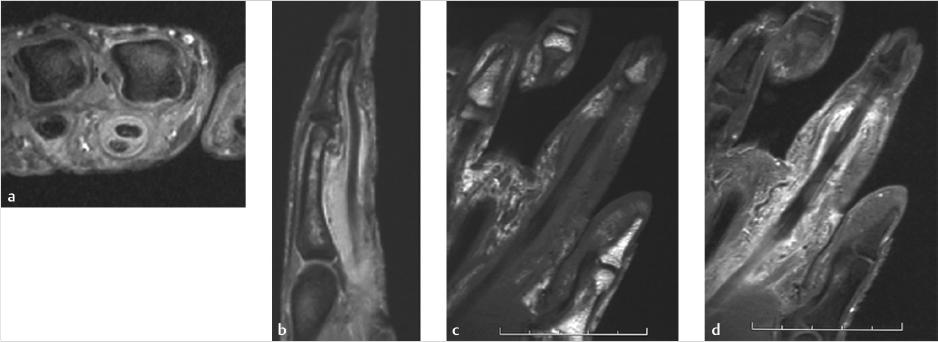

Imaging studies do not play a significant role in diagnosing purulent flexor tenosynovitis and may delay treatment. Depending on the history, a plain film may be beneficial to ensure that there is not an occult foreign body. Soft tissue gas on plain films may be indicative of a more nefarious process, such as a necrotizing infection. In cases that are questionable, magnetic resonance imaging (MRI)is the study of choice for the assessment of these patients (► Fig. 87.2).